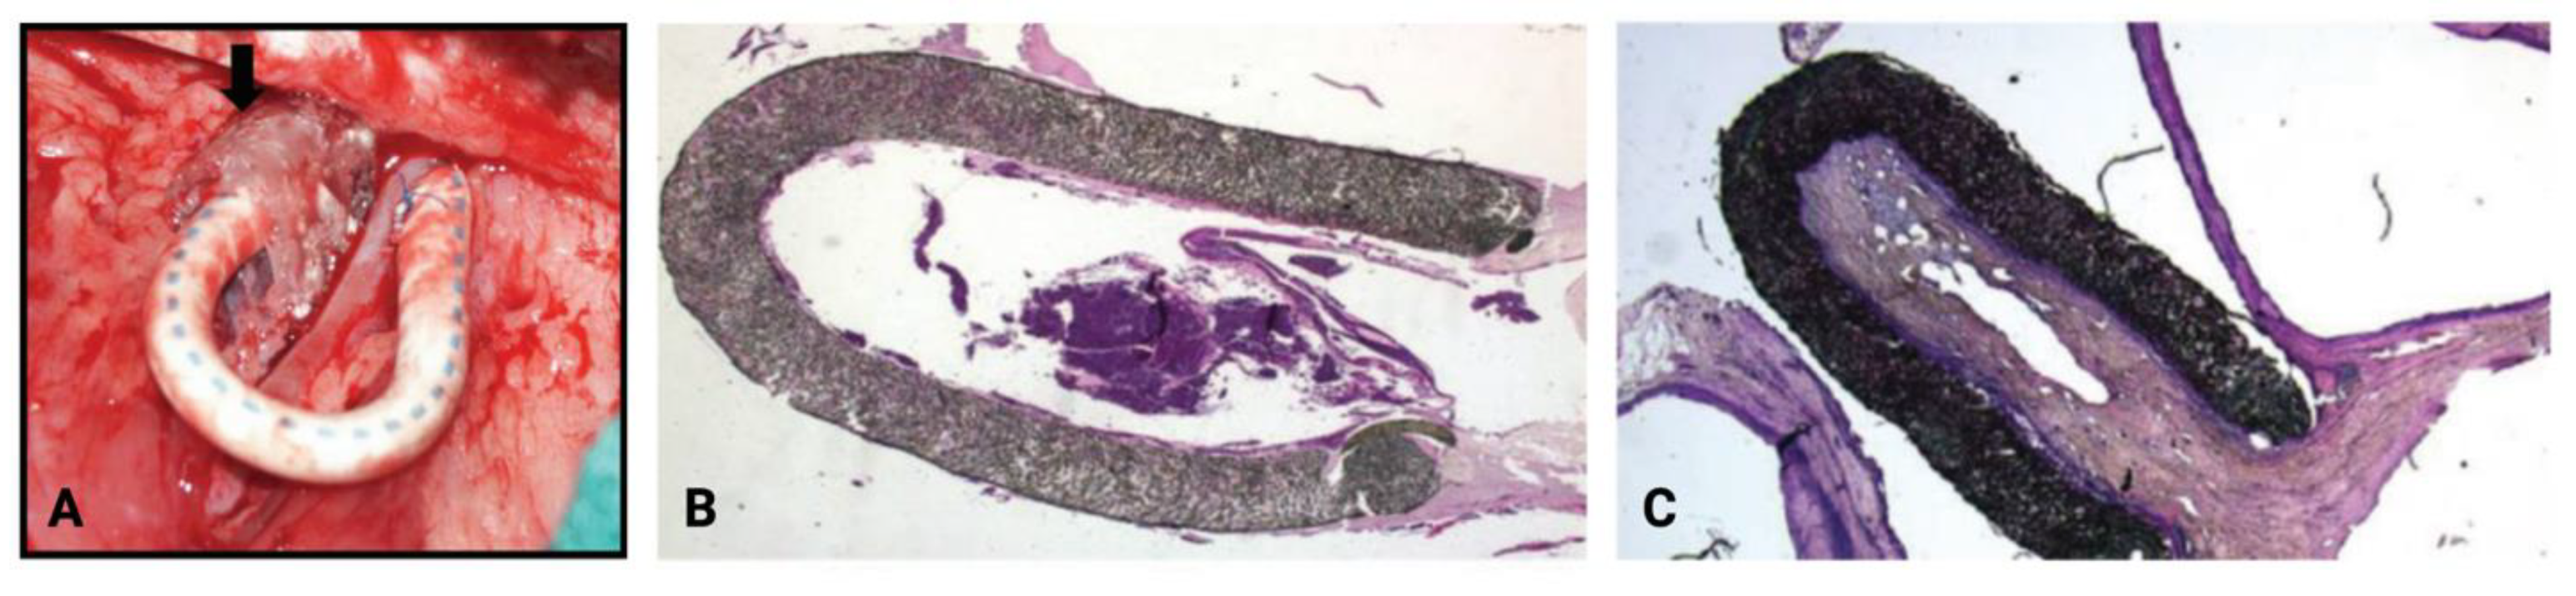

4.1. Mechanical Devices

4.3. Perivascular Cell-Based Therapeutics

4.3.1. Endothelial Cells

4.3.2. Mesenchymal Stem/Stromal Cells